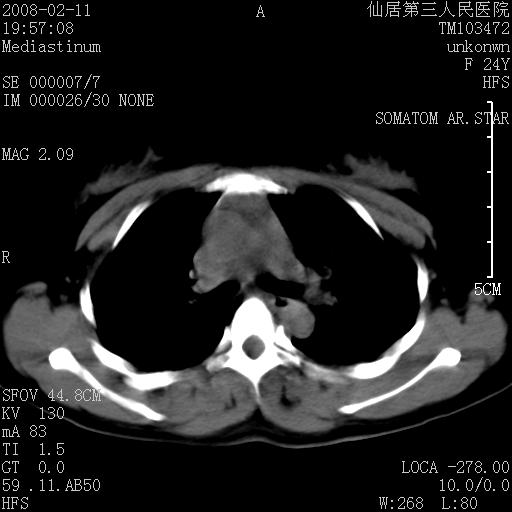

以下是引用zjzjr在2008-2-12 14:32:00的发言:[br]胸腺大点,是不是胸腺瘤或胸腺增生